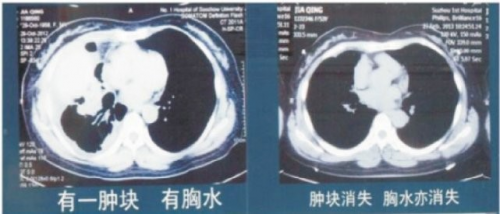

病例4:肺腺癌病例,贾青,女,55岁,2012年10月体检发现右上肺4cm肿块,CT示右上肺癌伴两肺散在性结节病理确诊为肺腺癌EGFR,突变型。至2012年12月病情进展并发胸水,因拒绝放、化疗,经应用参苓白术散,牛黄醒消丸及易瑞沙,临床症状消失。CT复查右上肺肿块消失,胸水亦消失。